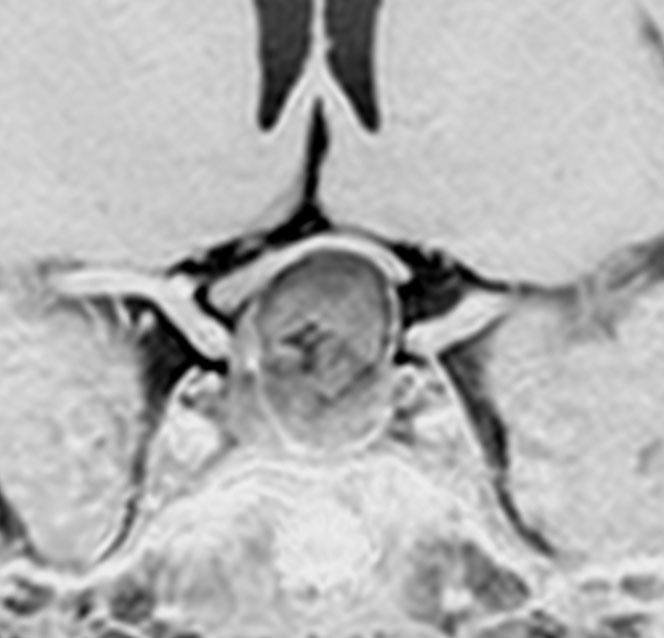

左と中央の画像でinfundibular recessの管腔が見え,左の視交差から視索の変形が強いことが解ります。右の画像では下垂体組織がトルコ鞍の右側に偏在してあります。画像では正常化錐体と明瞭な境界があるように見えるのですが,実際の手術所見では正常下垂体との境界は不鮮明でした。腫瘍のう胞からは黒褐色の内容液 machinery oil とコレステリン結晶が流出しました。厚いのう胞壁は硬膜と下垂体に強く付着して剥離するのが困難で切断して摘出しました。ラトケのう胞とはのう胞壁の厚さが異なると言えます。

術後5ヶ月のMRIです,無理して全摘出しませんでしたので残存腫瘍のように見えます。病理診断では,出血,慢性炎症性細胞浸潤を伴い,コレステリン結晶やヘモジデリンの沈着,泡沫組織球,多核巨細胞浸潤を伴った繊維性組織片に,少量の上皮組織塊があり,少量の正常下垂体組織も付着していると報告されました。施設によってはこの所見をラトケのう胞と病理診断するかもしれません。

術後には軽度の尿崩症がでましたが,1年半でデスモプレッシンを中断できて,下垂体機能は正常化しました。

1年半を要して残存腫瘍は徐々に縮小しました。この画像は術後3年半のもので,正常下垂体がトルコ鞍右側に偏って見えます。